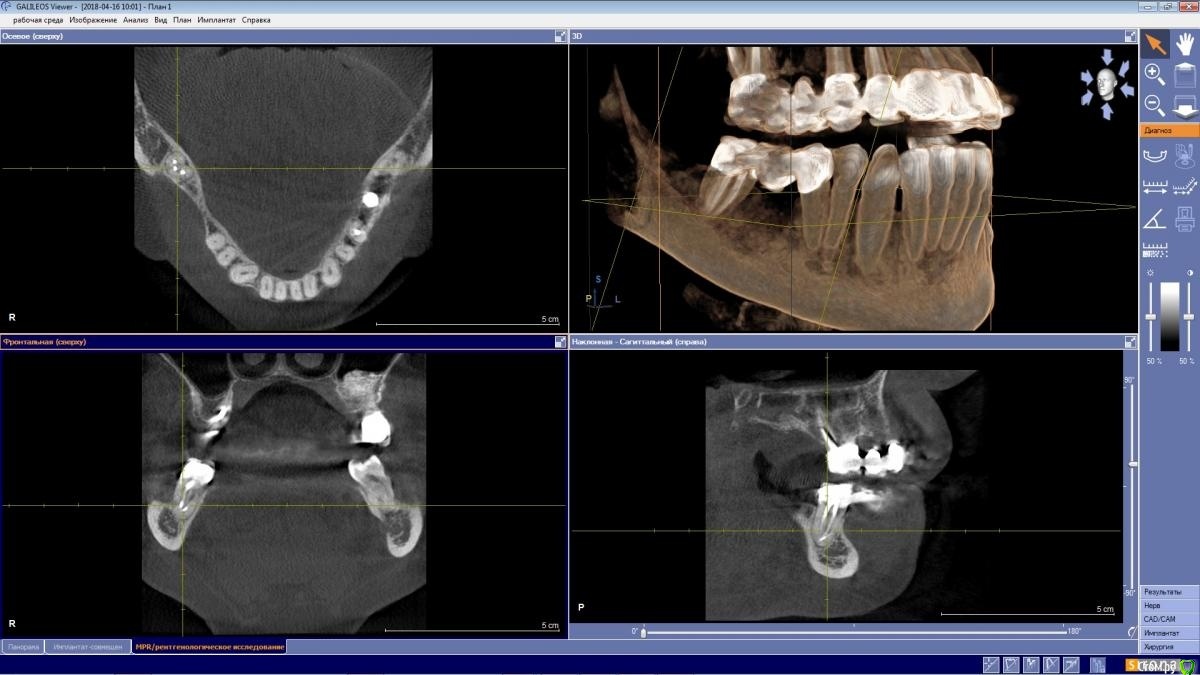

wladdX Опубликовано 25 октября, 2020 Поделиться Опубликовано 25 октября, 2020 КТ 04.2018. Я дополнительных каналов не увидел, может коллеги что рассмотрят. Ссылка на комментарий

ellenchik Опубликовано 26 октября, 2020 Автор Поделиться Опубликовано 26 октября, 2020 КТ 04.2018. Я дополнительных каналов не увидел, может коллеги что рассмотрят.1.jpg2.jpgСпасибо ,wladdX! Может врачи форумные еще что-то по снимкам подскажут. Ссылка на комментарий

St. Опубликовано 26 октября, 2020 Поделиться Опубликовано 26 октября, 2020 Да, в плане каналов все красиво. То есть все найдены и запломбированы на всю длину корня, и воспаления за пределами зуба не видно.Возможно, беспокоила десна Ссылка на комментарий